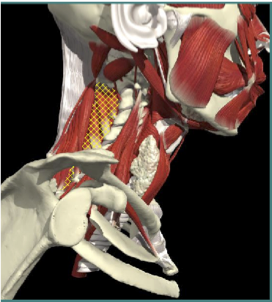

ACCURACY OF MUSCLE LOCALIZATION

- Muscles deep

- Not easily identified by surface landmarks

- Not palpable on examination

ACCURACY OF LOCALIZATION - SCALENES

ACCURACY OF LOCALIZATION LEVATOR SCAPULAE

LOCALIZATION OF MUSCLES IN DEEPER LAYERS

Layer 1

Layer 2

Layer 3

Splenius Capitis

Semispinalis Capitis

Longissimus Capitus

Semispinalis Cervicis

ACCURACY OF LOCALIZATION – DEEPER LAYERS

INJECTION SITES